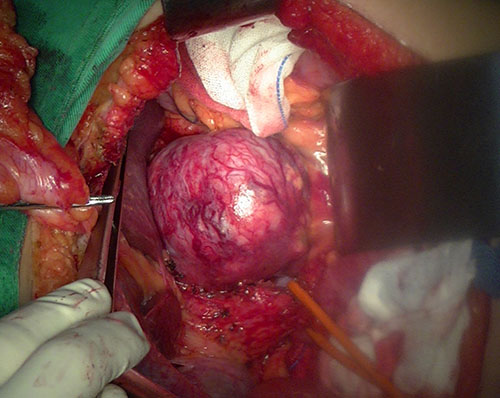

尾状叶肿瘤--尾状叶切除